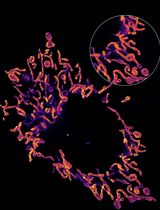

https://applications.zeiss.com/C125792900358A3F/0/8DF1FE51A0C52599C1257C1D0073F96D/$FILE/EN_41_011_061_ELYRA.pdf for microscope setup). - Locate sample using eyepiece and set up a 2 dimensional (2D), 2 color dSTORM (Endesfelder and Heilemann, 2015) experiment using the 488 nm and 641 nm excitation laser lines in separate tracks with the appropriate filters (a possible setup for this pair of dyes would be BP420-480/BP495-560/LP650). See Figure 2 (left) for parameter settings in Zen software.

- Locate a cell and position it in the center of the field of view (FOV) then refocus, ensuring that the entire cell membrane is clearly in focus (Figure 2 [right] for example image).

Figure 1. STORM imaging set-up. 1. Microscope: Axio Observer, Z1 (inverse stand); Incubator XL dark; Motorized Piezo XY scanning stage; Z-Piezo stage insert; Port for LSM attachment; two camera ports. 2. Objectives: Plan-APOCHROMAT 100x/1.46 Oil (DIC). 3. ELYRA Illumination and Detection: Fiber coupled solid state and diode pumped solid state lasers; 405 nm diode (50 mW); 488 nm OPSL (100 mW); 561 nm OPSL (100 mW); 642 nm diode (150 mW); Andor iXon 897 EM-CCD camera. 4. Software: ZEN (black edition), PALM module.

- Co-ordinates of the localizations in the final reconstructed images (typically 30,000+ for HER2 and 5,000+ for HER3 per region, Figure 3) are passed into the Bayesian cluster identification algorithm designed by Dylan Owen et al. (Griffié et al., 2016).